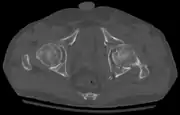

Axial CT image (viewed on bone windows) of a complex comminuted left acetabular fracture involving both anterior and posterior columns.

In all cases, CT scan can assist in identifying impacted bone pieces, which may be found within the joint, and MRI may be done to identify the extent of potential injury to the sciatic nerve.